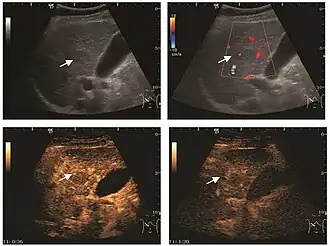

HCC appearance on 2D ultrasound is that of a solid tumor, with imprecise delineation, with heterogeneous structure, uni- or multilocular (encephaloid form). An "infiltrative" type is also described which is difficult to discriminate from liver nodular reconstruction in cirrhosis. Typically HCC invades liver vessels, primarily the portal veins but also the hepatic veins . Doppler examination detects a high speed arterial flow and low impedance index (correlated with described changes in tumor angiogenesis). The spatial distribution of the vessels is irregular, disordered. CEUS examination shows hyperenhancement of the lesion during the arterial phase. During the portal venous phase there is a specific "wash out" of ultrasound contrast agent (UCA) and the tumor appears hypoechoic during the late phase. Poorly differentiated tumors may have a stronger wash out leading to an isoechoic appearance to the liver parenchyma during portal venous phase. This appearance was found in approx. 30% of cases. The described changes have diagnostic value in liver nodules larger than 2 cm.

These lesions have various patterns (hypo or hyperechoic) with at least 1 cm diameter. They are hepatocytes with dysplastic changes, but without clear histological criteria for malignancy. They are divided into low-grade dysplastic nodules, where cellular atypia are mild and high-grade dysplastic nodules with moderate or severe cellular atypia, but without any established signs of malignancy. Occasionally, well-differentiated HCC foci can be identified in high-grade dysplastic nodules (appearance called "nodule in nodule") . Most authors accept the carcinogenesis process as a progressive transformation of DN from low-grade to high-grade and into HCC. The nodule's vasculature changes progressively, correlated with the degree of malignancy, and it is characterized by decrease until absence of portal venous input and by increase of arterial intratumoral input. Neoformation vessels occur with increasing degree of dysplasia. Arterial neovascularization is enhanced in a chaotic and explosive way, while normal, arterial and portal vasculature continues to decline. High-grade dysplastic nodules are hypovascularized both arterial and portal phases, while early HCC nodules may have similar arterial pattern with the surrounding parenchyma or exacerbated, and portal hypovascularization. In moderate or poorly differentiated HCC (classic HCC) tumor nutrition is performed only by neoformation vessels (abundant), the normal arterial and portal vasculature completely disappearing. This behavior of intratumoral vascularization is typical for HCC and is the key to imaging diagnosis.

B-mode ultrasonography is unable to distinguish between regenerative nodules and borderline lesions such as dysplastic nodules and even early HCC. Doppler examination also has a low sensitivity in differentiating dysplastic nodules from early HCC. Doppler signal may be absent in both regenerative and dysplastic nodules. Some authors indicate the presence of venous type Doppler flow which reflects the portal venous nutrition of the nodule as a characteristic feature of dysplastic nodules and early HCC (Minami & Kudo, 2010). Other authors noticed the presence of an arterial flow with small frequency variations and a normal resistivity index. On CEUS examination both RN and DN may have quite a variable enhancement pattern. Generally, both nodules enhances identically with the surrounding liver parenchyma after UCAs injection. Dysplastic nodules are hypovascular in the arterial phase. In case of highgrade dysplastic nodule sometimes a hypervascularization can be detected, but without associating "wash out" during portal and late CEUS phases. In these cases, biopsy may clarify the diagnosis.

Spectral Doppler characteristics of early HCC overlap those of the dysplastic nodule, as they are represented by the presence of portal venous signal type or arterial type with normal RI (well differentiated HCC) or increased RI (moderately or poorly differentiated HCC). The CFM exploration identifies a chaotic vessels pattern.

On CEUS examination, early HCC has an iso- or hypervascular appearance during the arterial phase followed by wash out during portal venous and late phase. There are studies showing that the wash out process is directly correlated with the size and features of neoplastic circulatory bed. Thus, highly differentiated HCC illustrates the phenomenon of late or even very late "wash out" while poorly differentiated HCC has an accelerated wash out at the end of arterial phase. It is therefore mandatory to analyze all these three phases of CEUS examination for a proper characterization of liver nodules. Tumor wash out at the end of the arterial phase allows the HCC diagnosis with a predictability of 89.5%. Some authors consider that early pronounced contrast enhancement of a nodule within 1–2 cm developed on a cirrhotic liver is sufficient for HCC diagnosis. These results prove that for a correct characterization of the lesions it is necessary to extend the examination time to 5 minutes or even longer.